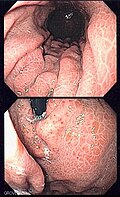

Gross

Features:[22]

- Mosaic-like pattern.

- May be referred to as snakeskin-like pattern.[23]

- Usu. body of stomach.

- +/-Red spots.

Images